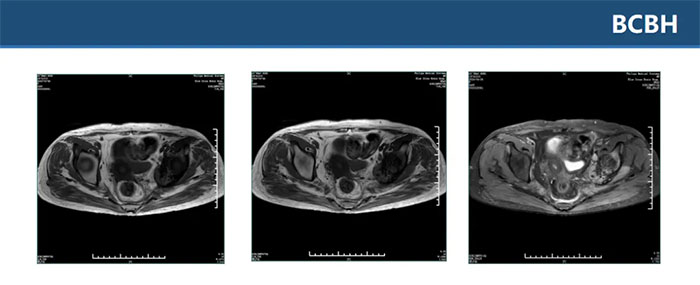

▲ 雙側(cè)坐骨、髂骨、骶骨、左側(cè)恥骨多發(fā)異常信號(hào)伴左髂骨髖臼處骨質(zhì)破壞,考慮腫瘤性病變,轉(zhuǎn)移瘤待排